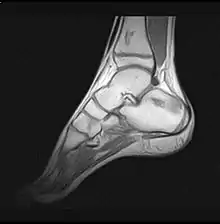

یک تصویر ام آر آی از پاشنهٔ پا با دید ساژیتال

از این دید در تصویرگیریهای ام آر آی نیز استفاده میشود. گاه به جای واژه "دید" در این موضوع از واژههای "برش" یا "مقطع" نیز استفاده میشود .